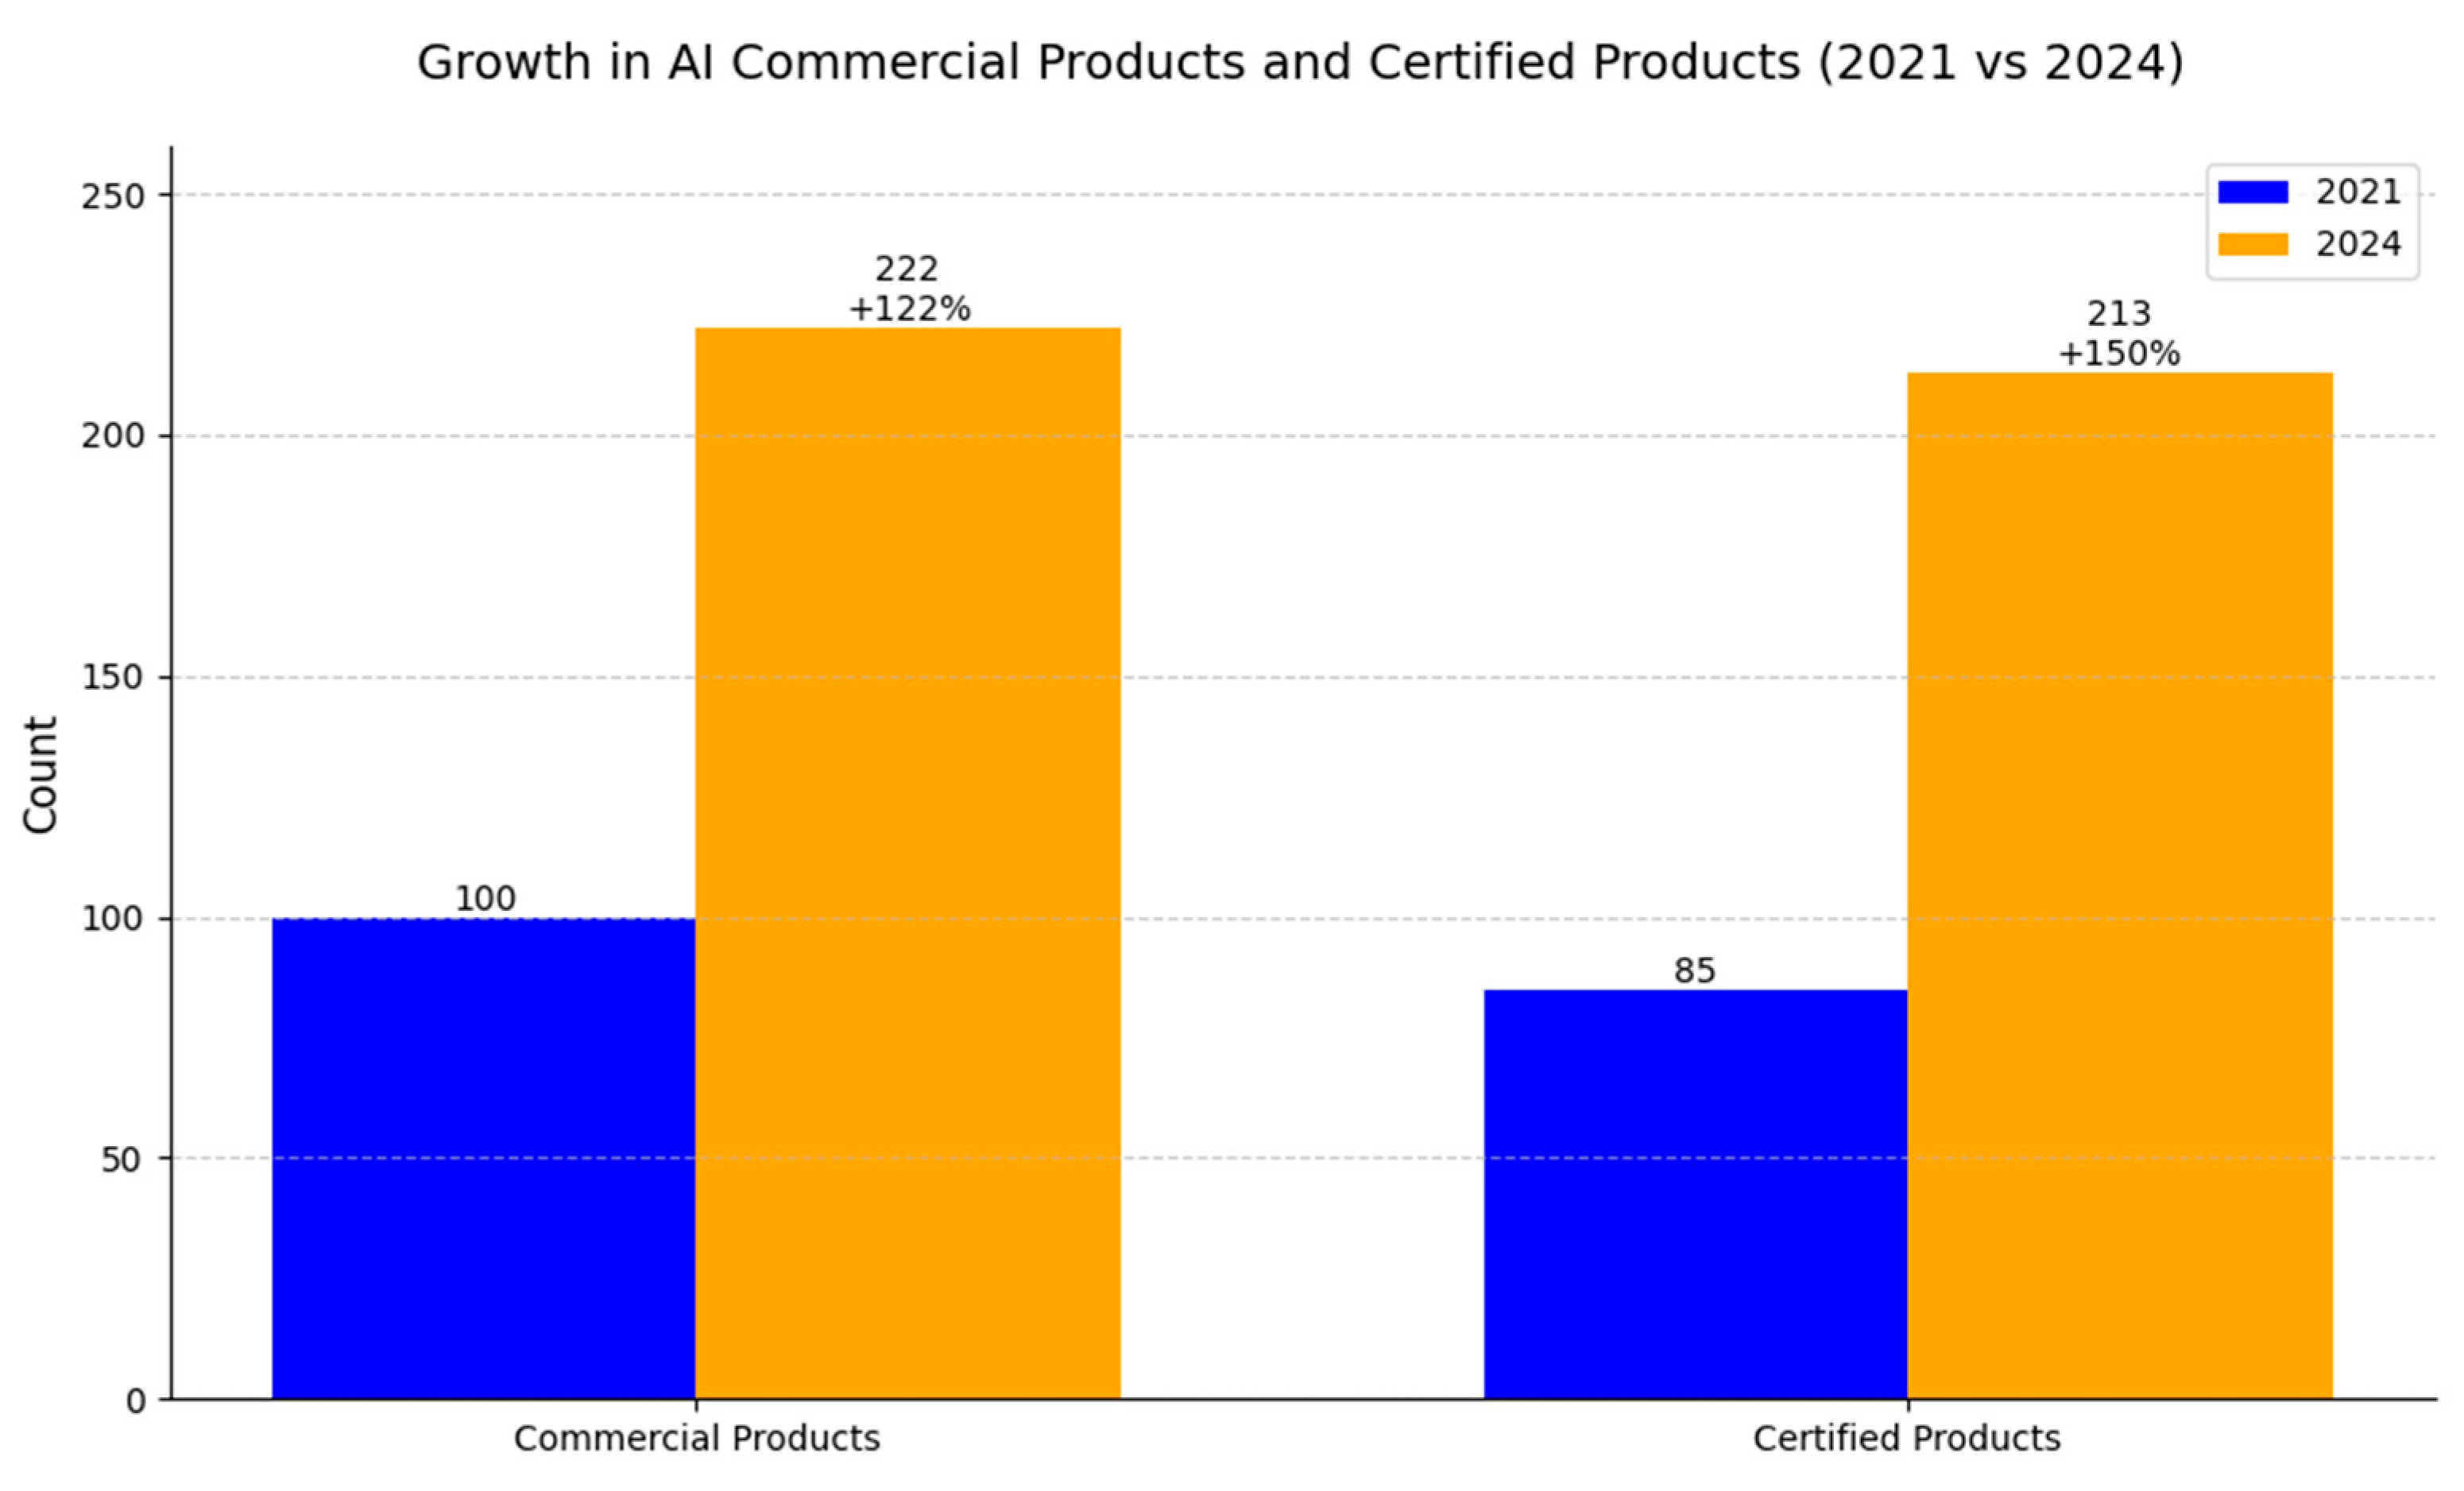

9. Review of AI Products Used in Radiology: Status in 2024

- Van Leeuwen, K.G.; Schalekamp, S.; Rutten, M.J.C.M.; Van Ginneken, B.; De Rooij, M. Artificial Intelligence in Radiology: 100 Commercially Available Products and Their Scientific Evidence. Eur. Radiol. 2021, 31, 3797–3804. [Google Scholar] [CrossRef]

- Zhu, S.; Gilbert, M.; Chetty, I.; Siddiqui, F. The 2021 Landscape of FDA-Approved Artificial Intelligence/Machine Learning-Enabled Medical Devices: An Analysis of the Characteristics and Intended Use. Int. J. Med. Inform. 2022, 165, 104828. [Google Scholar] [CrossRef] [PubMed]